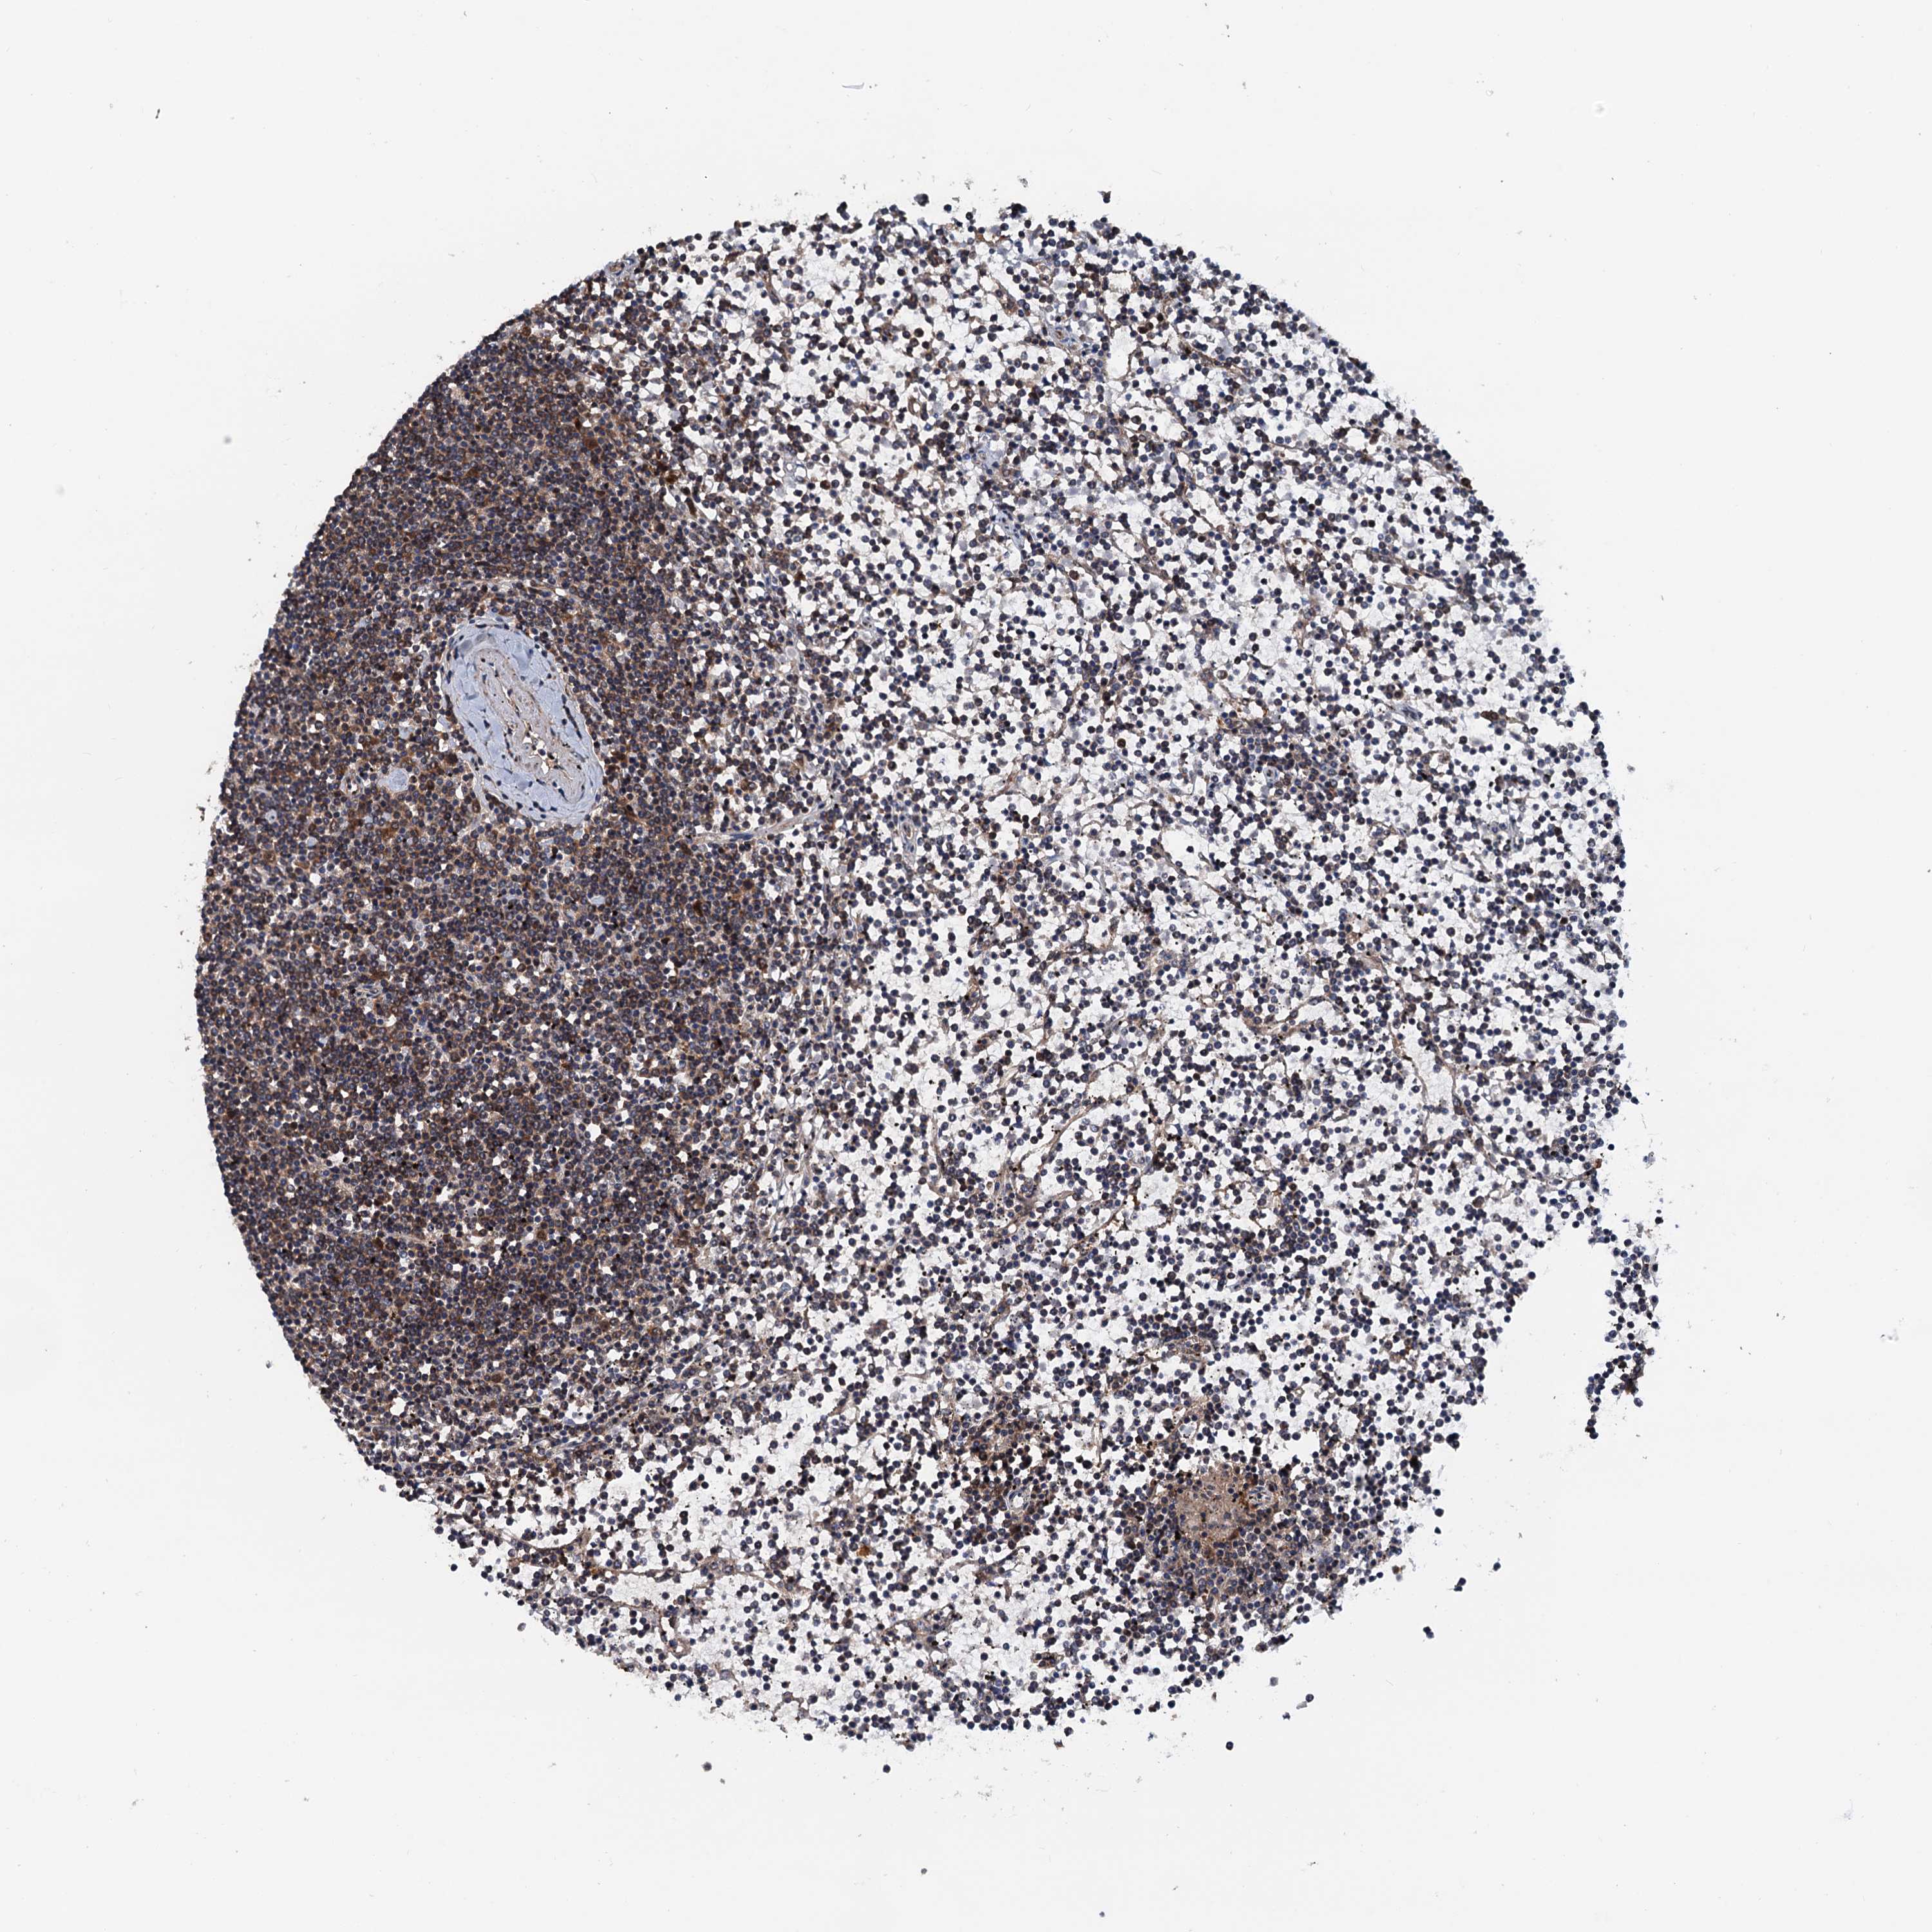

LYMPHOMA - Protein expressioni

A mouse-over function shows sample information and annotation data. Click on an image to view it in a full screen mode. Samples can be filtered based on level of antibody staining by selecting one or several of the following categories: high, medium, low and not detected. The assay and annotation is described here.

Antibody staining in the annotated cell types in the current human tissue is reported as not detected, low, medium, or high, based on conventional immunohistochemistry profiling in selected tissues. This score is based on the combination of the staining intensity and fraction of stained cells.

Each image is clickable and will lead to virtual microscopy that enables deeper exploration of all samples and also displays staining intensity scores, fraction scores and subcellular localization as well as patient and tissue information for each sample.

Hodgkin's disease, NOS

Malignant lymphoma, non-Hodgkin's type, High grade

Malignant lymphoma, non-Hodgkin's type, Low grade